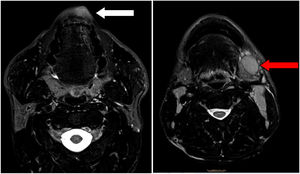

Se realizó una resonancia magnética cervical que mostró una pequeña lesión labial central izquierda en el labio inferior con diámetro axial mayor de 17 mm, no infiltrativa. Adenopatías patológicas laterocervicales bilaterales, pero de predominancia izquierda que sugerían un proceso linfoproliferativo (fig. 1).